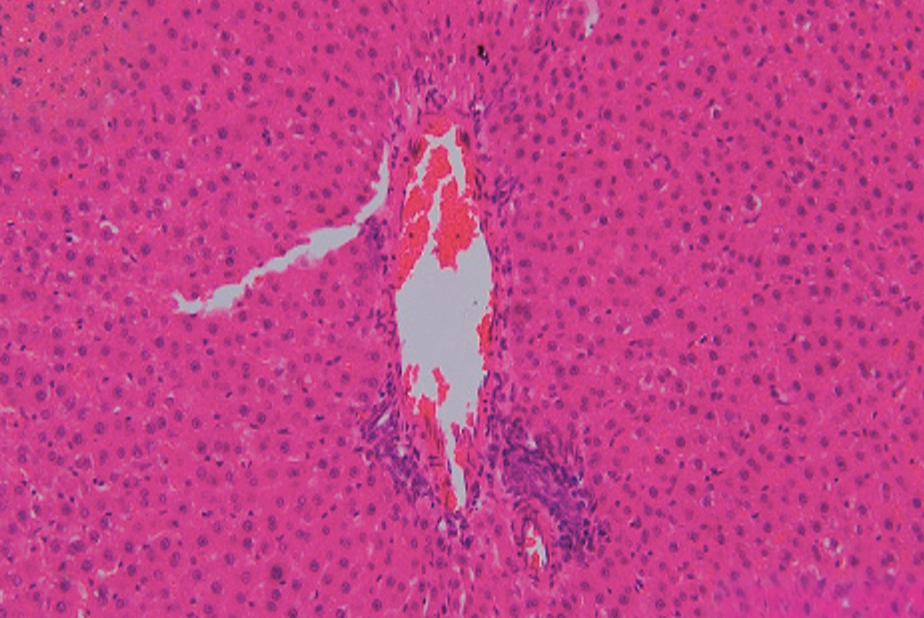

- Esami istopatologici: gli esami del fegato e dei reni hanno mostrato lievi anomalie, come vacuolizzazione e congestione vascolare, che non sono state associate a cambiamenti significativi nei marcatori biochimici.